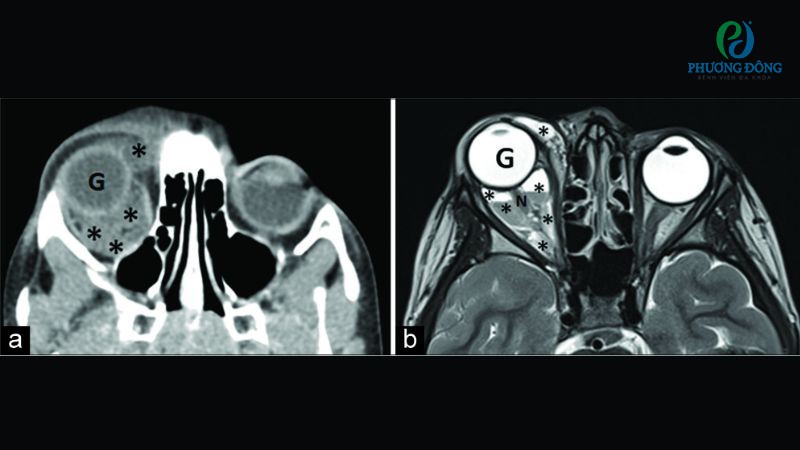

- Chụp CT kiểm tra những khối u hình thành từ xương mắt, cấu trúc quanh hốc mắt để xác định phương pháp phẫu thuật hiệu quả.

- Chụp MRI cho hình ảnh chi tiết về các mạch máu, dây thần kinh và khối u. Từ dữ liệu thu được, bác sĩ đánh giá được sự lan rộng của khối u, các tổ chức liên quan, đặc biệt hữu ích với những trường hợp phức tạp.

Chụp CT, MRI đầu não chẩn đoán phân biệt khối u hốc mắt với các bệnh lý thần kinh khác